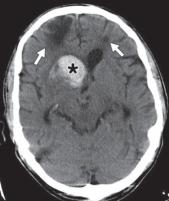

图 6A—淀粉样血管病。未增强 CT 图像识别出以右侧基底神经节为中心的急性出血(星号),提示高血压原因。血肿被血管源性水肿的薄边缘包围并延伸到右额角。两额叶出现慢性脑软化灶(箭头)。

其他微血管病大脑受累的分布不同。在淀粉样血管病中,多灶性和脑叶出血性中风很常见。GRE/磁敏感加权成像可用于检测隐匿性微出血病灶(图6A 、 6B, 和6C)。

2.2出血

血管源性水肿常见于继发于高血压、外伤、凝血病、淀粉样血管病、血管异常、中风和转移瘤的大面积颅内出血附近。据推测,该机制涉及血凝块形成过程中血清蛋白的渗出,导致血肿周围炎症和血脑屏障破坏。水肿在 CT 扫描上表现为周围低密度,在 MR 图像上表现为 T2/FLAIR 高信号。有时,它可能会产生高达原始病变体积两倍的占位效应(图6A , 6B, 和6C)。可以进行医疗管理以降低升高的颅内压。即将发生的脑疝可能需要手术清除和去骨瓣减压术。